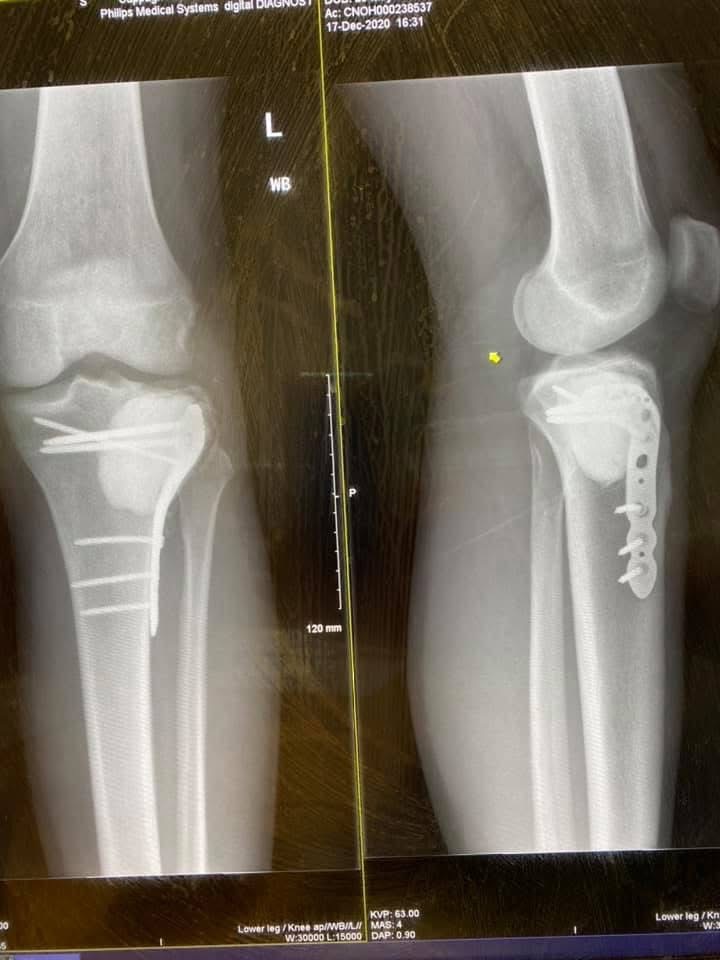

I’m hoping to raise some money for the Cappagh Orthopaedic Hospital Dublin Foundation. For those of you who may not know, back in 2020 i was diagnosed with having a Giant Cell Tumour in my knee. A Giant Cell Tumour is a rare benign tumour but locally agressive. I had this initial tumour removed, followed by a reoccurence a year after. All was well until a sepsis scare at Christmas 2022 had me under go a couple of more sugeries and take too many antibiotics!!

After a long road, some screws, a metal plate and a bit of concrete, The knee is now better than ever and I’m so excited to be running this years marathon, which is something I never thought would be possible.